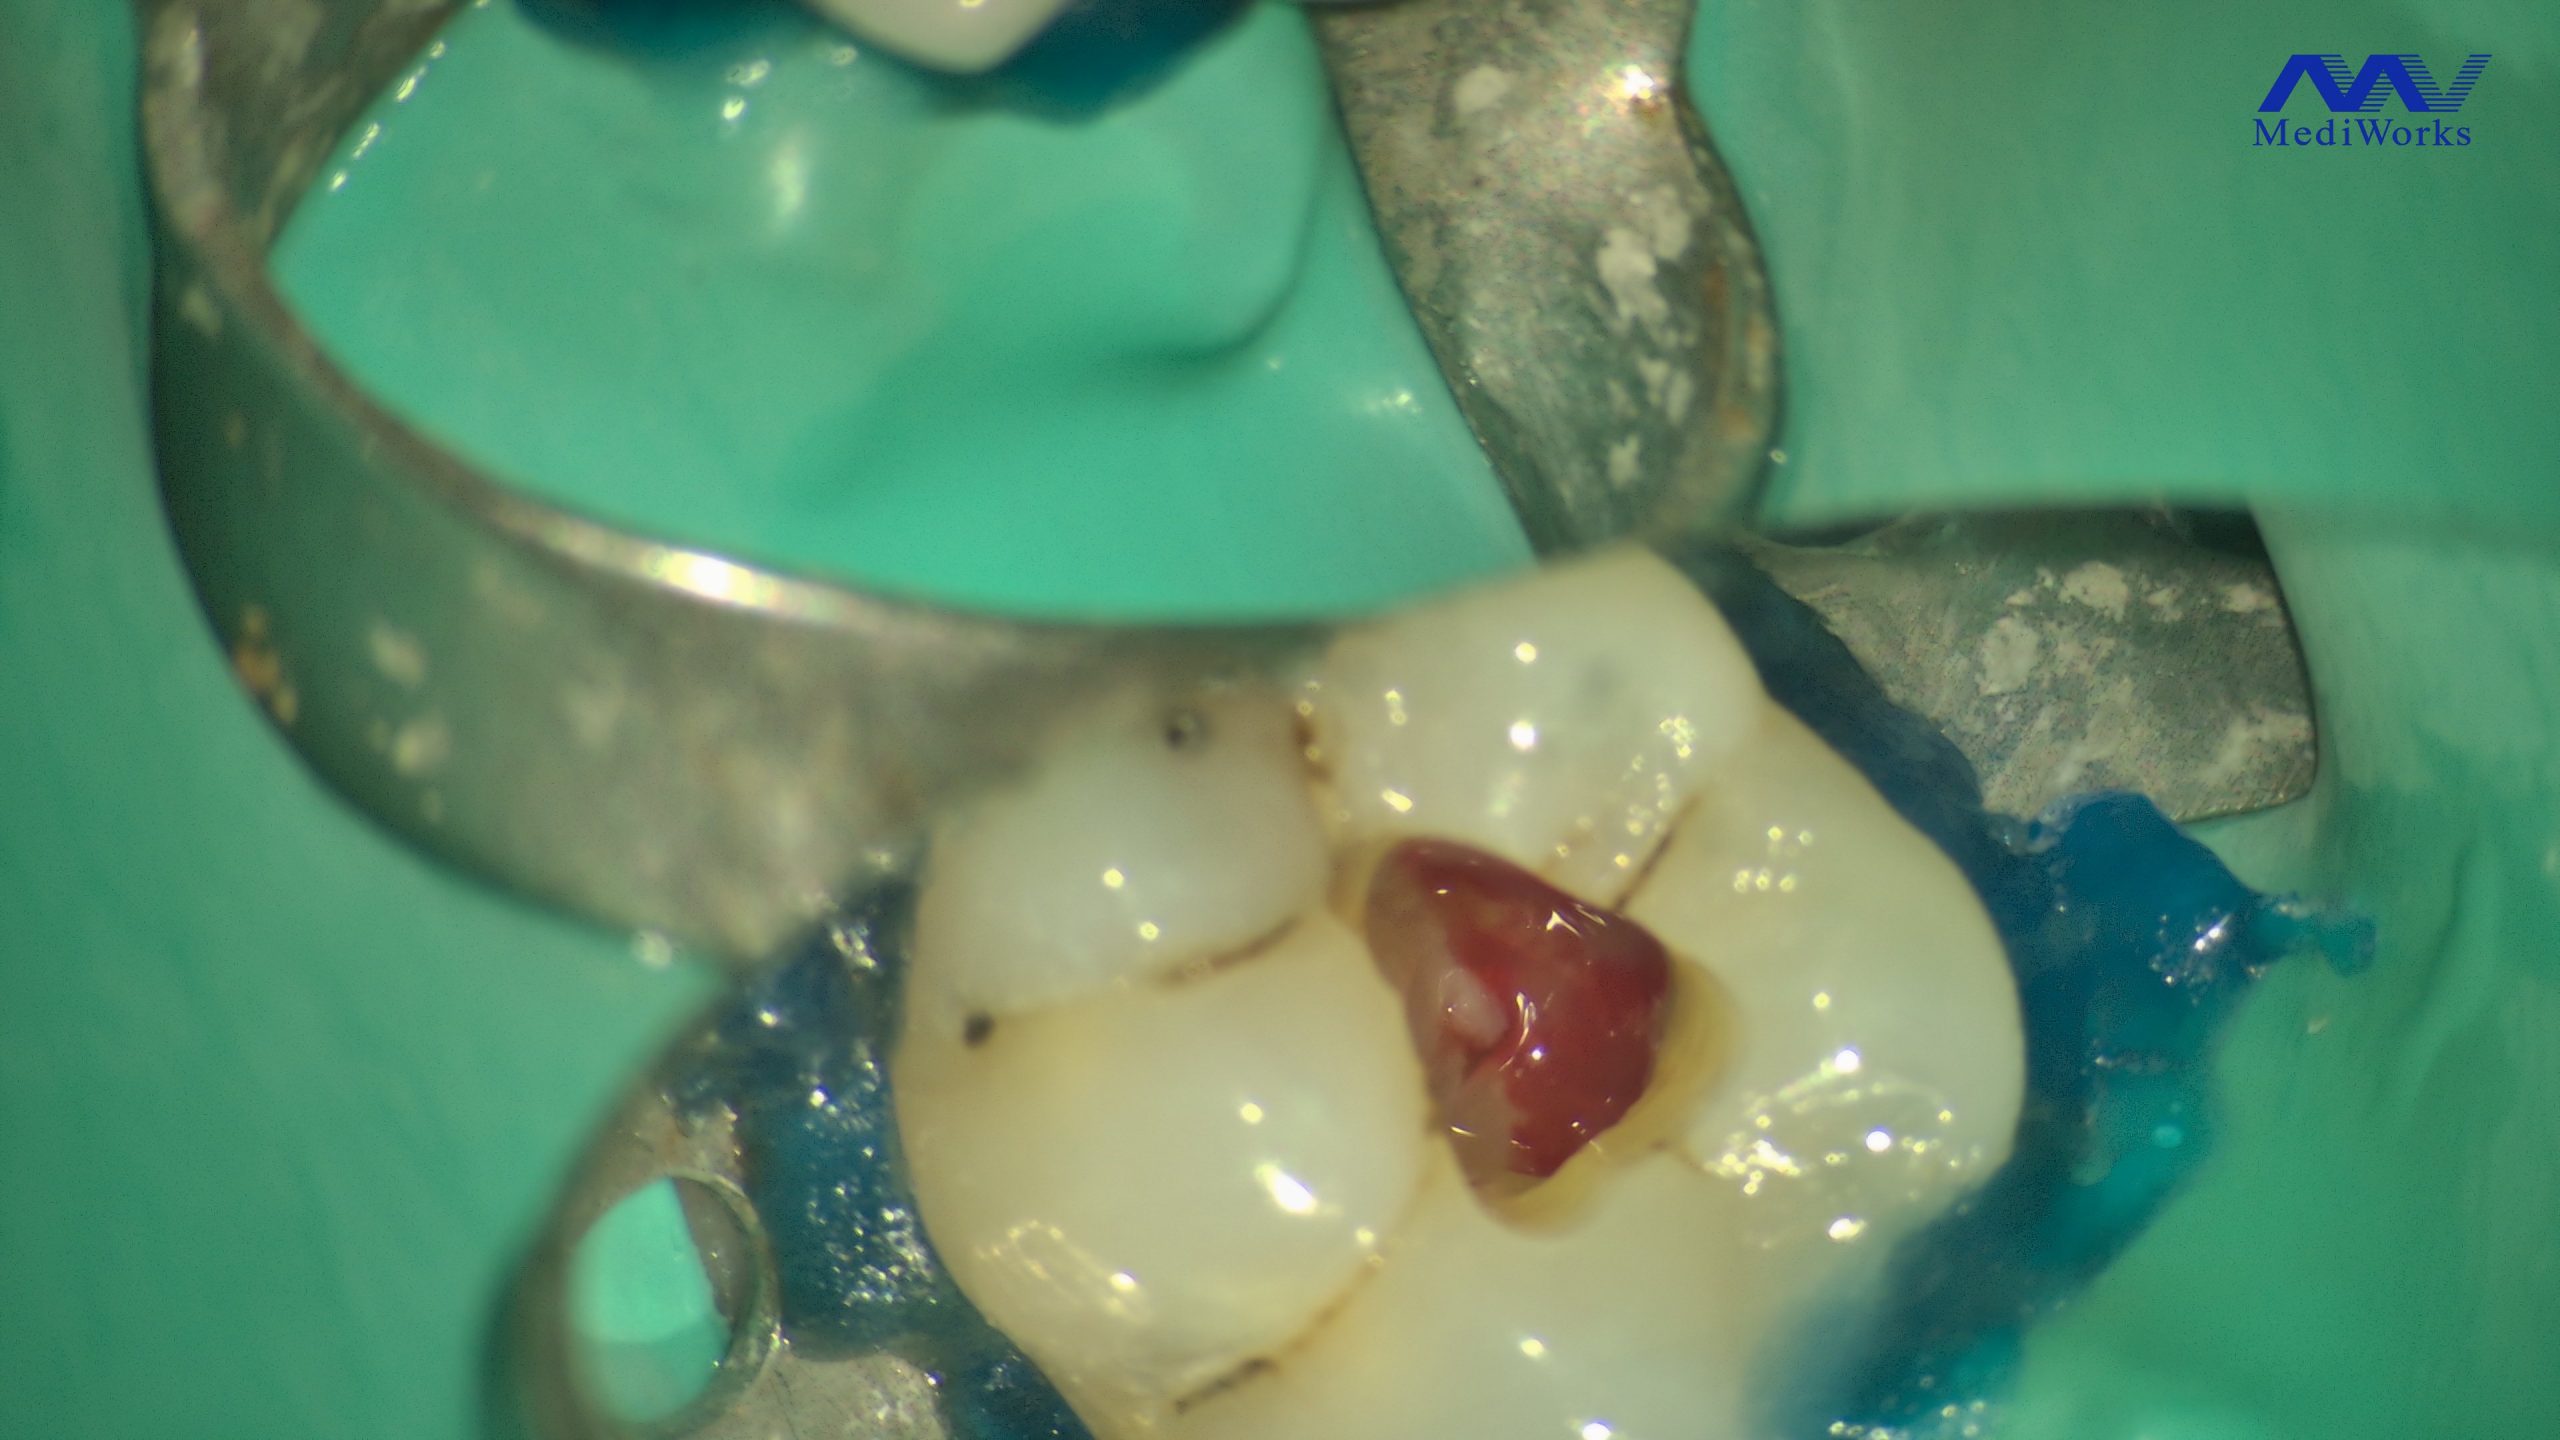

Formation centrée sur la maîtrise de l’endodontie moderne, depuis le diagnostic jusqu’à l’obturation, avec des protocoles fiables et applicables immédiatement au cabinet. Le programme alterne théorie clinique, analyse de cas réels et travaux pratiques intensifs afin d’améliorer la prise en charge des traitements endodontiques initiaux.

La formation aborde également les causes d’échec en endodontie et les stratégies de retraitement à travers une approche pragmatique : gestion des canaux complexes, butées, fausses routes, désobturation, interprétation du CBCT et prise de décision clinique, appuyées par des cas commentés et des exercices pratiques guidés.

Une journée complète pour maîtriser le traitement endodontique initial (TEI), du raisonnement diagnostique aux gestes clés de l’accès, de la mise en forme, de l’irrigation et de l’obturation. Le matin, théorie structurée + cas cliniques pour fixer les principes efficaces et reproductibles. L’après-midi, travaux pratiques pour s’approprier les techniques et les protocoles que vous pourrez appliquer dès le lendemain au cabinet.